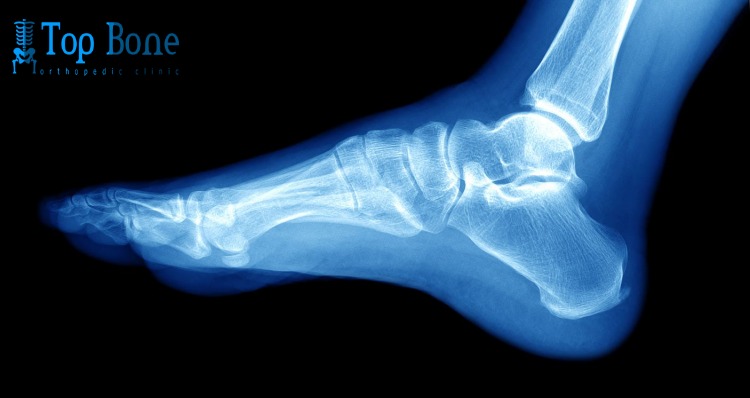

تعد عملية تثبيت مفصل الكاحل من العمليات الشائعة والمهمة في طب العظام، حيث تهدف إلى تثبيت المفصل في موضعه الطبيعي بعد تعرضه لإصابة أو تلف، مما يساعد على استعادة الحركة الطبيعية للكاحل. يلجأ الطبيب إلى هذا الإجراء عادةً عند فشل الأدوية في تخفيف آلام الكاحل الناتجة عن التهاب المفاصل الحاد.

تعد كسور الكاحل من أكثر الكسور صعوبة وذلك نظرًا لطبيعة البناء الهيكلي للكاحل، حيث يقع مفصل الكاحل في نقطة التقاء ثلاثة عظام بجانب العديد من الأربطة والأوتار. يُعد الرياضيين هم الأكثر عرضة للإصابة بكسور الكاحل وتأتي أهمية صحة مفصل الكاحل لكونه المفصل المسئول عن دعم وثبات الجسم أثناء الوقوف أو المشي أو أثناء ممارسة الأنشطة الرياضية.

عندما يحدث تلف في غضروف الكاحل يبدأ المريض بالشعور بالألم وتصلب المفصل، وفي هذه الحالة تكون عملية تثبيت مفصل الكاحل هي الحل الأفضل للمريض حتى يستطيع ممارسة حياته بشكل طبيعي، في هذه العملية يتم إزالة المفصل التالف واستبداله بمفصل اخر صناعي يقوم بنفس عمل المفصل الطبيعي.

هذه الجراحة هي عملية معقدة ولكنها تعيد للمريض حياته ونشاطه بشكل طبيعي، وفي جراحة تثبيت مفصل الكاحل تكون نهايات العظام مترابطة مما يجعل المفصل صلباً لكنه يساعدك على العودة إلى حركاتك الطبيعية.

عملية تثبيت مفصل الكاحل هي جراحة ينصح الأطباء بإجرائها للأشخاص الذين لا يمكنهم المشي بشكل طبيعي لان مفصل الكاحل لديهم به تلف شديد.